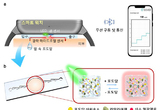

땀 한 방울로 혈당측정 기술 나왔다

- 2025-09-12 09:03

- - 기자